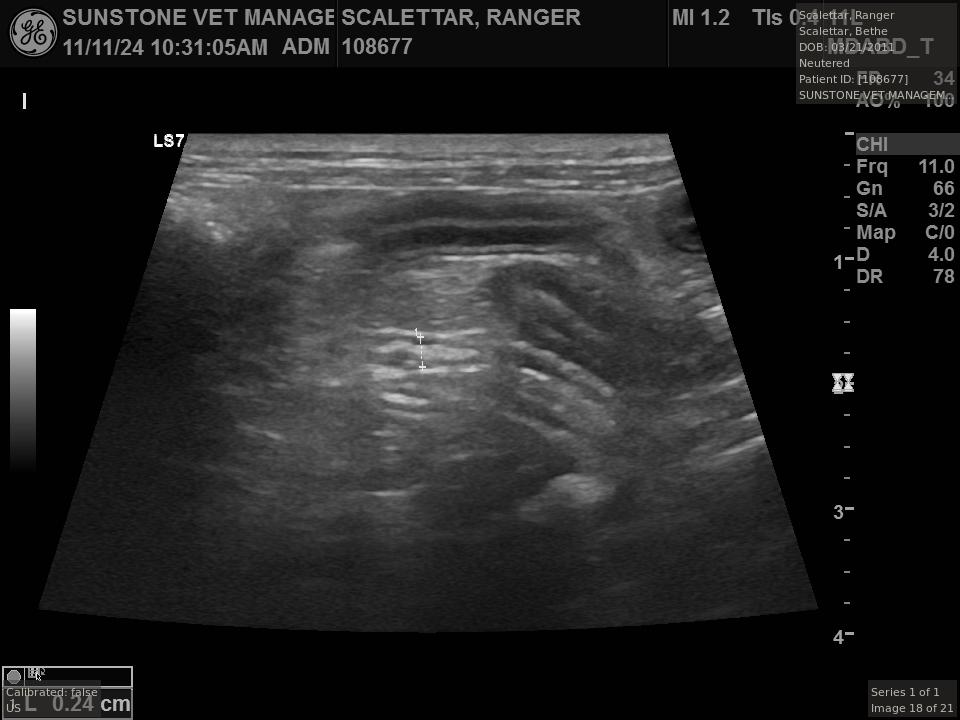

The veterinarian generated a series of images showing different organs and substructures by

changing the position and orientation of the ultrasound transducer. The images were collected

in a defined order, which is repeated from patient to patient, ensuring that nothing is missed. In

Ranger's case, the sonographer collected about twenty images during an examination that

lasted about fifteen minutes.

The sonographer stated that Ranger's ultrasound images were largely normal for an older cat. In particular, they show changes in the kidneys that are commonly noted in geriatric cats and that reflect a risk for the development of chronic kidney disease. However, the images did not show any significant abnormalities in Ranger's stomach, intestines, and associated lymph nodes. Nonetheless, the results did not rule out recurrence of Ranger's small cell lymphoma.